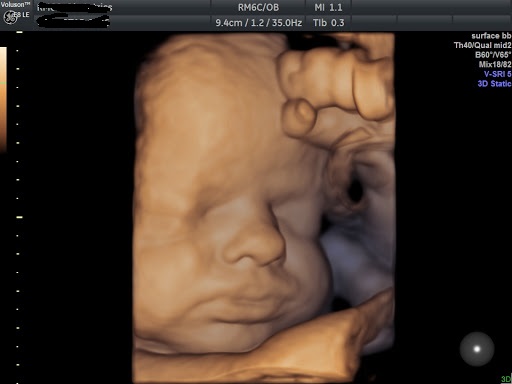

• Attualmente Medico Ginecologo presso "l'Unità Operativa" diagnosi prenatale della Clinica Mangiagalli di Milano.

- Gravidanza e principali patologie ostetriche, Ecografie ostetriche, Patologia ginecologica, Ecografia ginecologica. Infertilità.

Foto e Video